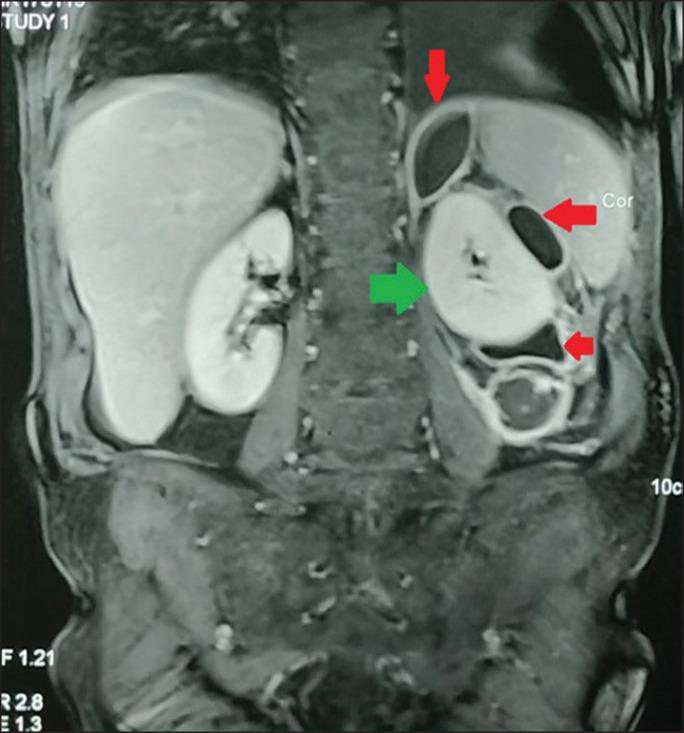

Pseudocysts in the perinephric region are rare and pose a diagnostic dilemma. We present the case of a 54-year-old male with left perirenal pancreatic pseudocyst. The diagnosis was enabled via proper clinical history taking and imaging investigations. The patient was successfully managed with definitive primary surgical treatment. This report highlights difficulties in diagnosis and treatment.

肾周区域的假性囊肿罕见,且会造成诊断上的两难局面。我们报告一例54岁男性左肾周胰腺假性囊肿病例。通过恰当的临床病史采集和影像学检查得以确诊。该患者通过确定性一期手术治疗获得成功处理。本报告强调了诊断和治疗方面的困难。